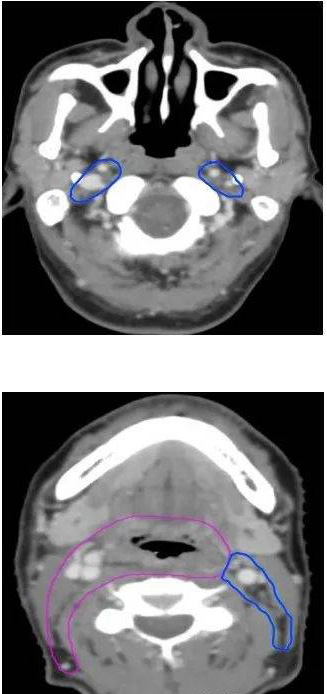

病例一:根治性放疗(下咽鳞癌T2N2bM0 IVA期,左侧梨状窝)

GTVp为肿瘤原发灶(由喉镜和CT、MRI、PET/CT等检查共同确定)

GTVn为阳性淋巴结(由CT、MRI、PET/CT等检查共同确定)

CTV1为高危亚临床病灶(包括左侧梨状窝原发灶、阳性淋巴结、同侧咽后及同侧淋巴引流区II-V区,全喉及相邻会厌前)

CTV2为低危亚临床病灶(包括对侧咽后及淋巴引流区II-IV区)

病例二:术后辅助放疗(下咽鳞癌T2N2bM0 IVA期,右侧梨状窝,右颈II-III区淋巴结转移

CTV1为高危亚临床病灶(包括术后瘤床区、同侧II-V淋巴引流区,全喉及相邻会厌前间隙,椎前筋膜间隙)

CTV2为低危亚临床病灶(包括双侧咽后淋巴结及对侧II-IV区淋巴引流区)